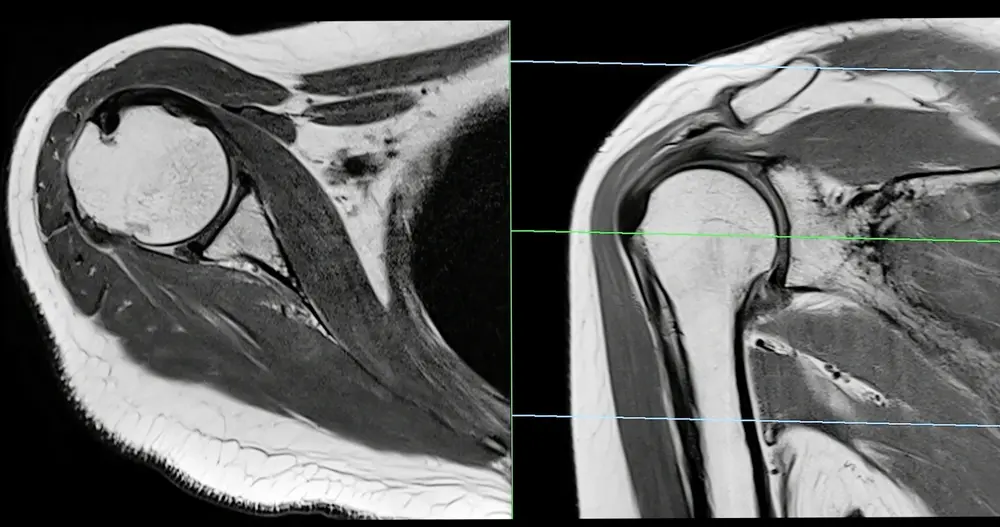

MRI scan of a shoulder joint showing detailed internal structures for diagnosing shoulder pain.

Magnetic resonance imaging shows detailed pictures of bones, ligaments, and soft tissue that X-rays cannot detect. A shoulder MRI or knee scan reveals hidden swelling and small tears that limit movement.